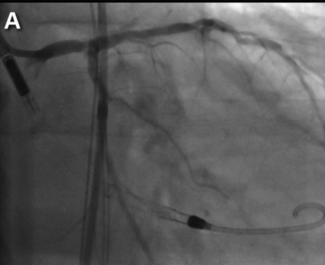

Transcatheter aortic valve implantation (TAVI) is nowadays the optimal therapeutic strategy in patients with severe aortic valve stenosis (AS). Consequently, percutaneous coronary intervention (PCI) of concomitant complex coronary artery...